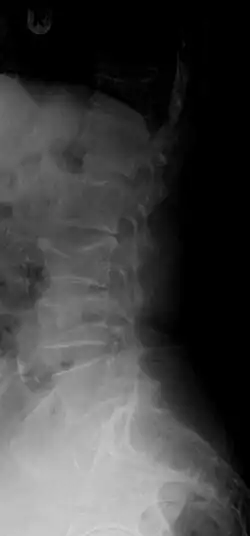

A compression fracture is a collapse of a vertebra. It may be due to trauma or due to a weakening of the vertebra (compare with burst fracture). This weakening is seen in patients with osteoporosis or osteogenesis imperfecta, lytic lesions from metastatic or primary tumors,[1] or infection.[2] In healthy patients, it is most often seen in individuals suffering extreme vertical shocks, such as ejecting from an ejection seat. Seen in lateral views in plain x-ray films, compression fractures of the spine characteristically appear as wedge deformities, with greater loss of height anteriorly than posteriorly and intact pedicles in the anteroposterior view.[3]

Compression fractures are usually diagnosed on spinal radiographs, where a wedge-shaped vertebra may be visible or there may be loss of height of the vertebra. In addition, bone density measurement may be performed to evaluate for osteoporosis. When a tumor is suspected as the underlying cause, or the fracture was caused by severe trauma, CT or MRI scans may be performed.

X-ray of the lumbar spine with a compression fracture of the third lumbar vertebra. -